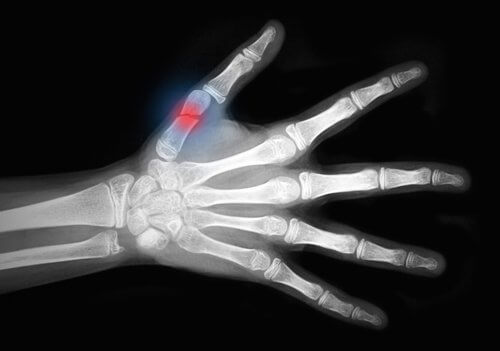

Esta doença enfraquece os ossos, tornando-os mais frágeis e propensos a quebrarem. Os ossos do punho, bem como os do quadril ou a coluna vertebral são os que correm mais risco de quebrar.